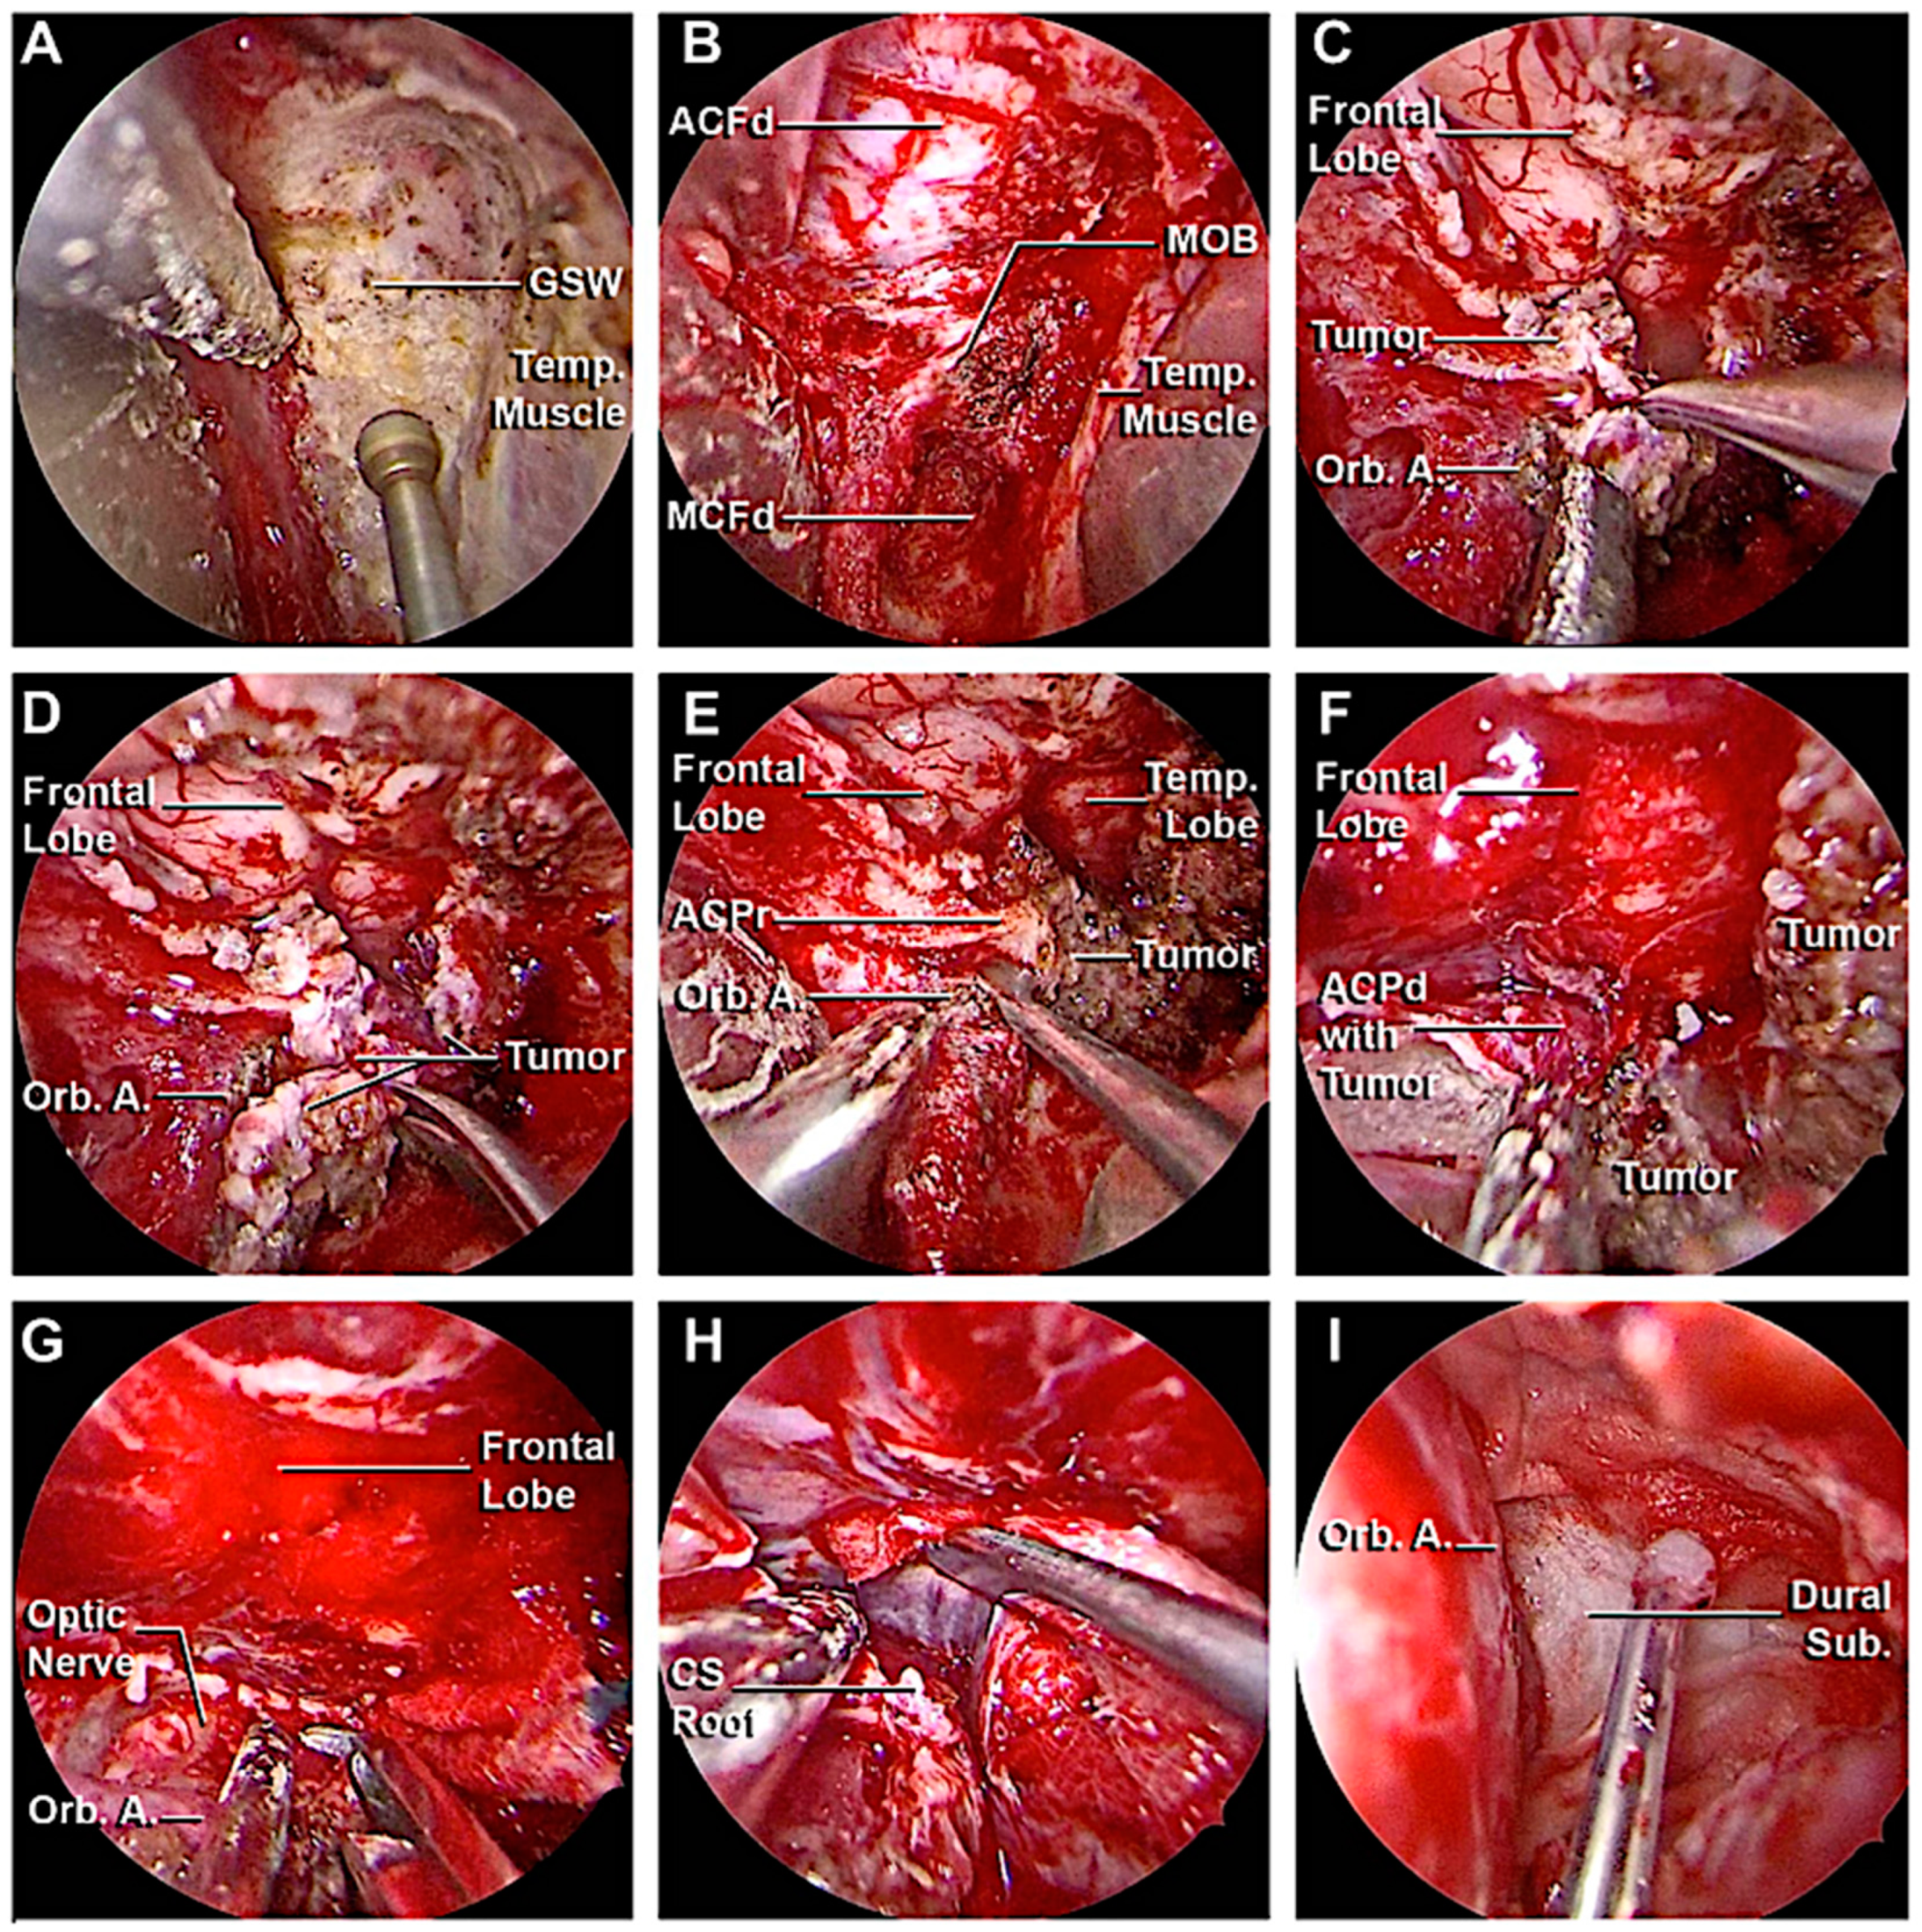

3.3. Clinical Cases

3.3.1. Case 1